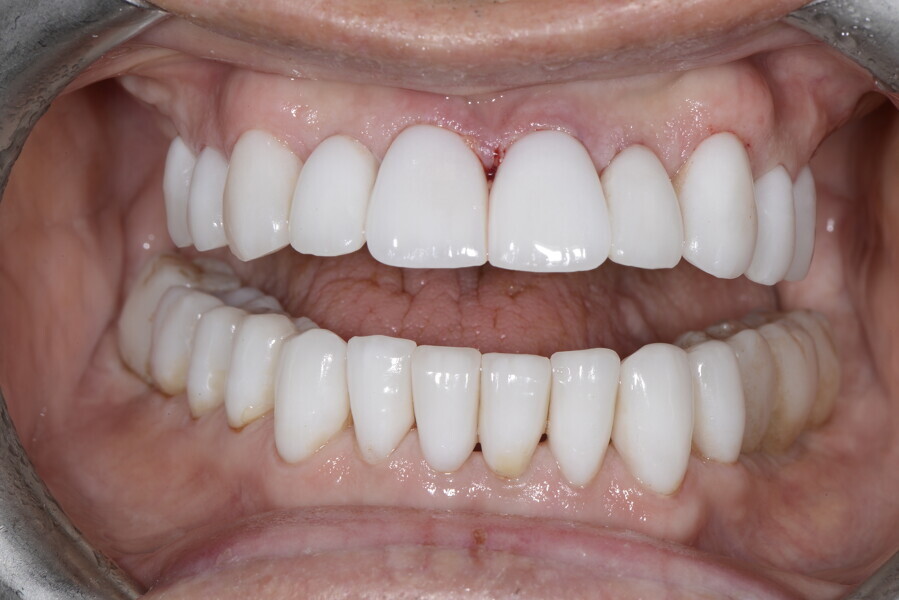

After the first phase of aligner treatment, we had achieved better inter-arch coherence, better maxillary arch expansion, and some space for improving the anterior tooth proportions restoratively (Fig. 19). We then temporarily restored the anterior teeth directly with composite, closing the spaces, improving the tooth proportions and further increasing the maxillary arch expansion (Fig. 20). We used restorative arch expansion to reduce the orthodontic destabilisation of the teeth to achieve the correct inter-arch coherence and retain the teeth in the cortical bone.38 A refinement aligner phase was undertaken to improve the final alignment of the gingival zenith and to improve the inter-arch coherence (Fig. 21). The periods of the first orthodontic phase and of the refinement were used to augment the mandibular and maxillary bone and to place the implants (Fig. 22). At the end of the orthodontic treatment, the case was finalised with ceramic veneers in the anterior area and temporary restorations on the implants in the posterior area (Figs. 23–26).

The provisional phase of about four months was important to allow the peri-implant tissue to mature and to teach the patient to chew correctly with chewing gum, cotton rolls and silicone masticatory sticks. This is fundamental training for the patient to achieve the correct alternating unilateral masticatory cycle needed to obtain the ideal rehabilitation of the masticatory system. We wanted the patient to achieve ideal masticatory and swallowing function. After sufficient rehabilitation time, we finalised the case with posterior zirconia crowns screwed on to the implants (Fig. 27).26